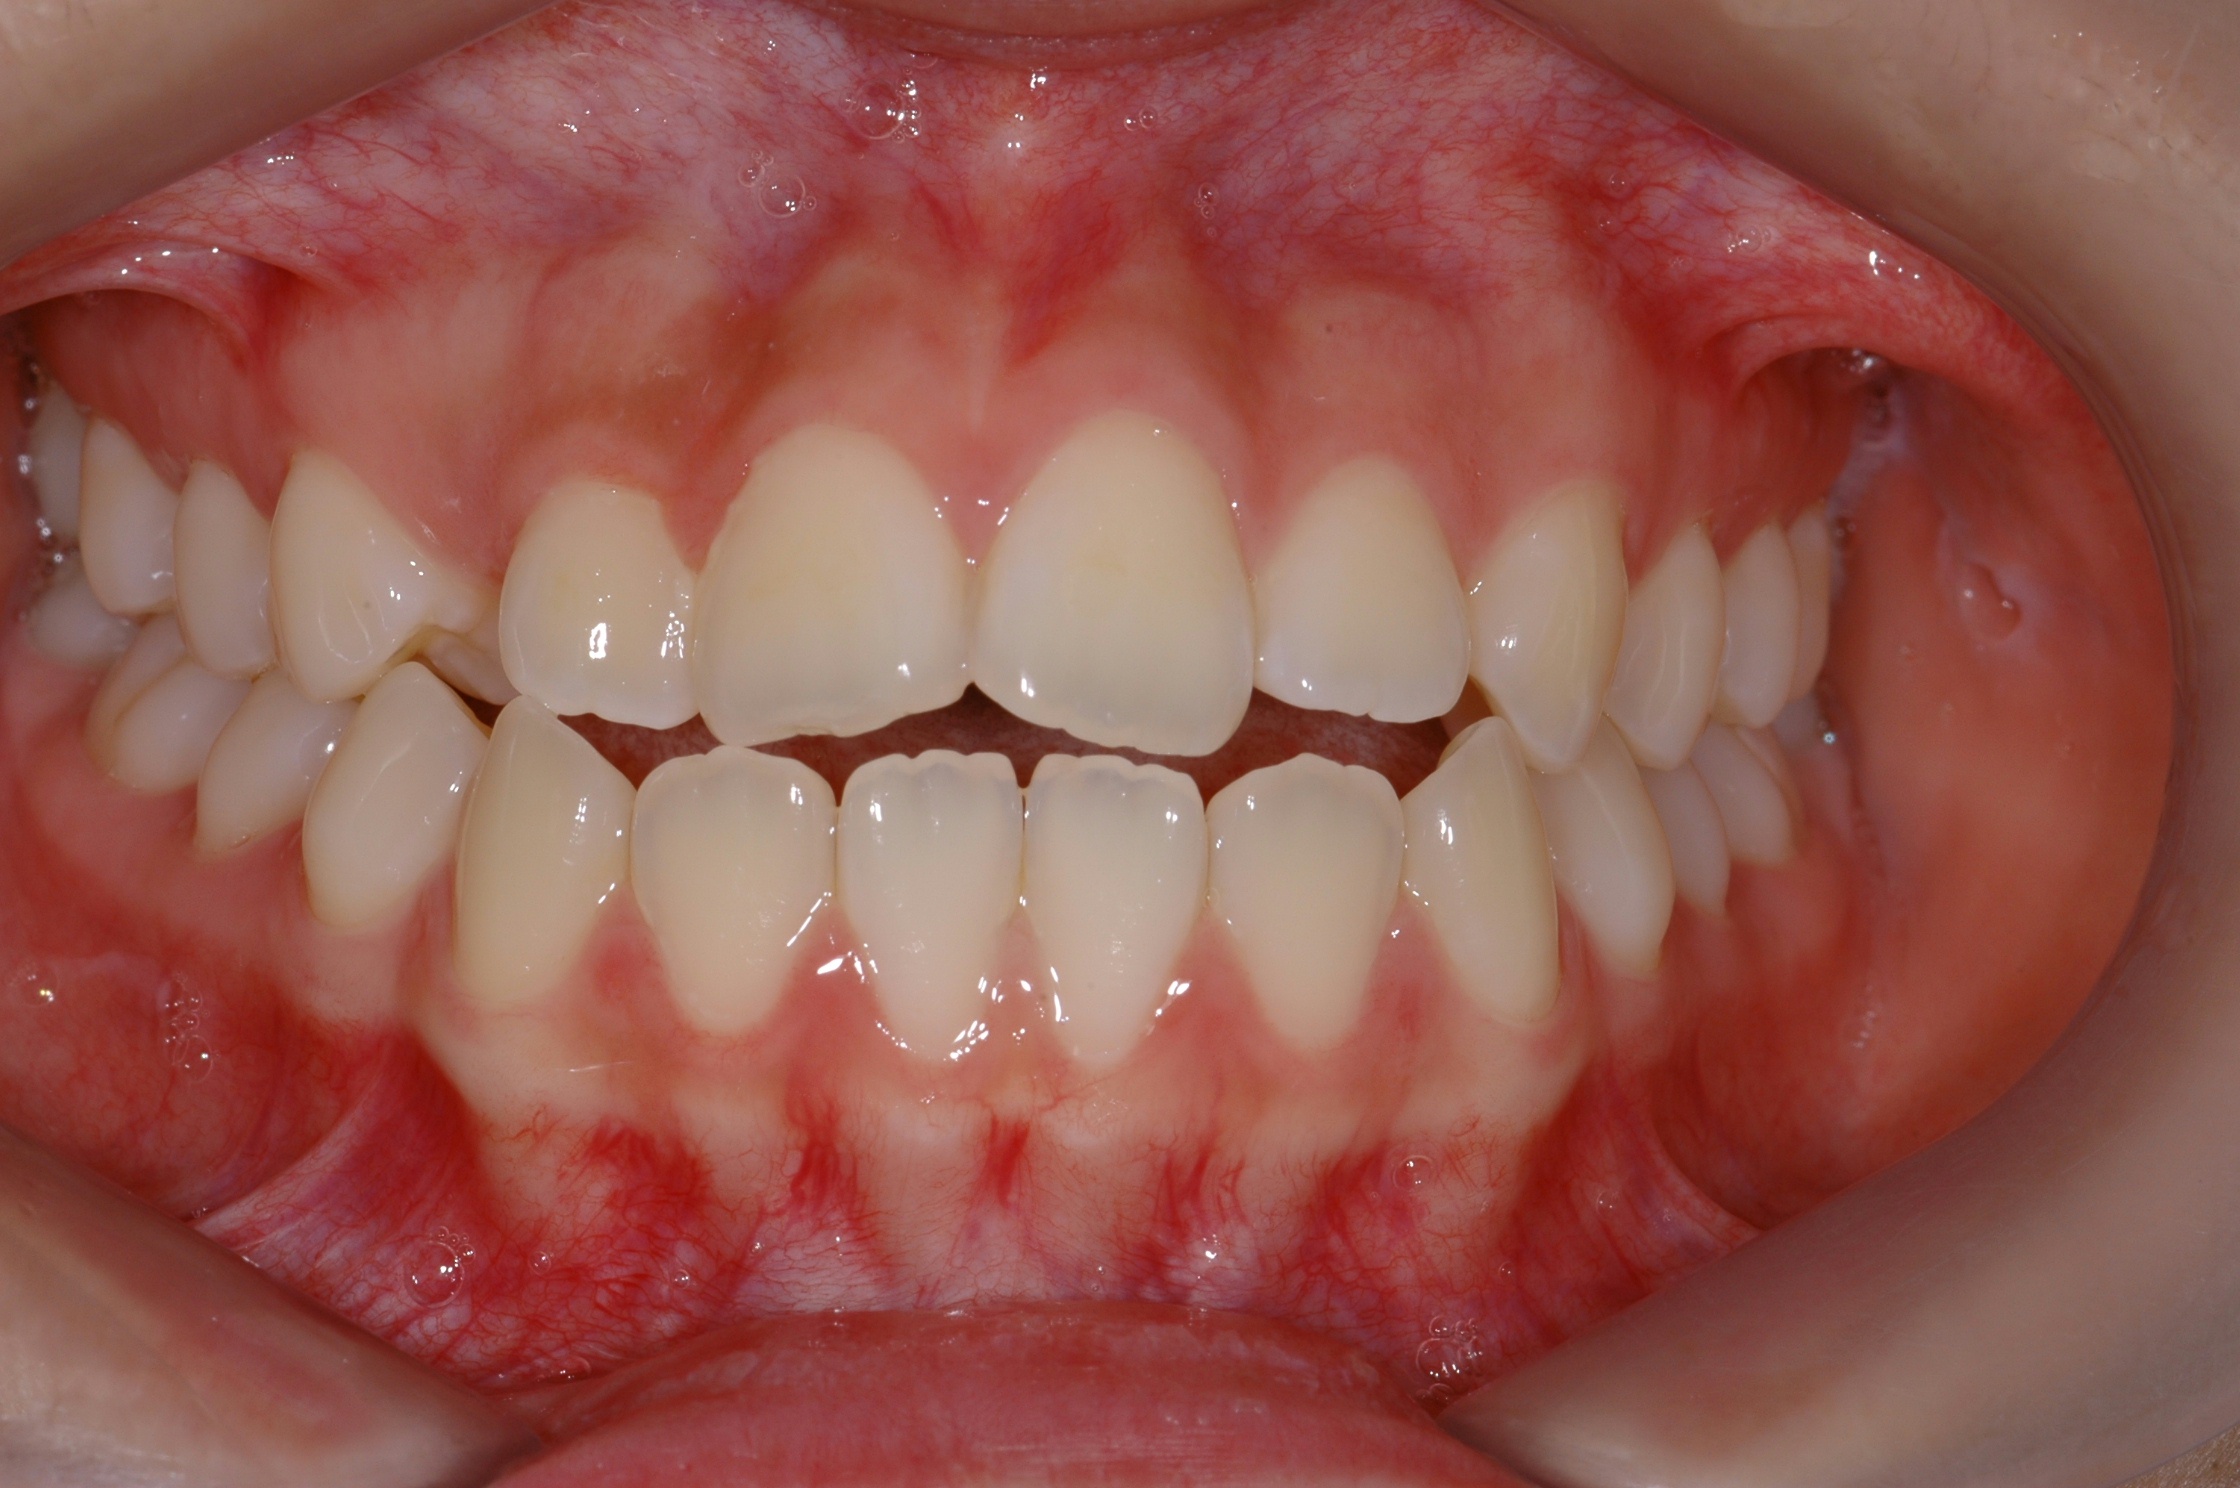

치료 전 사진입니다.